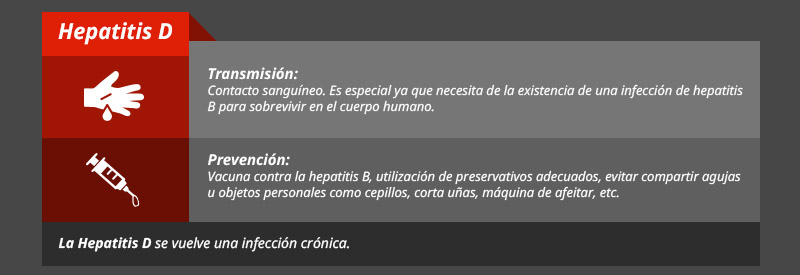

Tipos de hepatitis